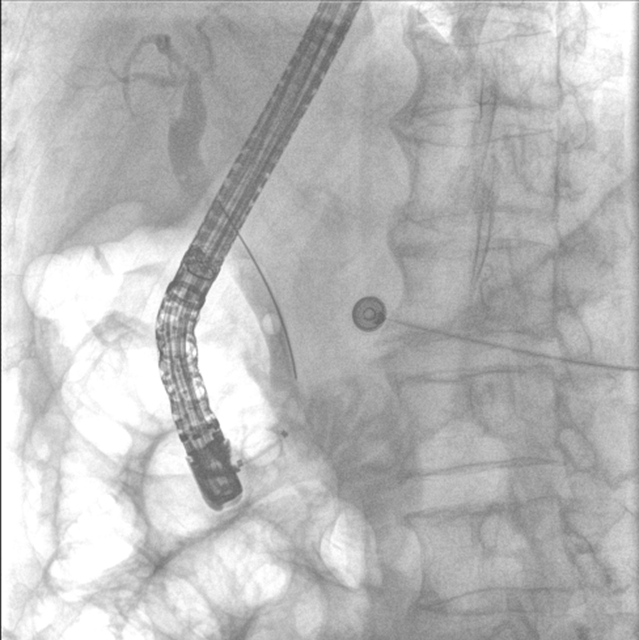

3.精准:“可视化”操作降低风险

内镜逆行胰胆管造影全程在X光和内镜直视下完成,医生能清晰看到结石位置、乳头形态,避免盲目操作。即使结石嵌顿严重(像"卡在墙缝里的石块"),也能通过球囊扩张或机械碎石取出,成功率高达90%以上。